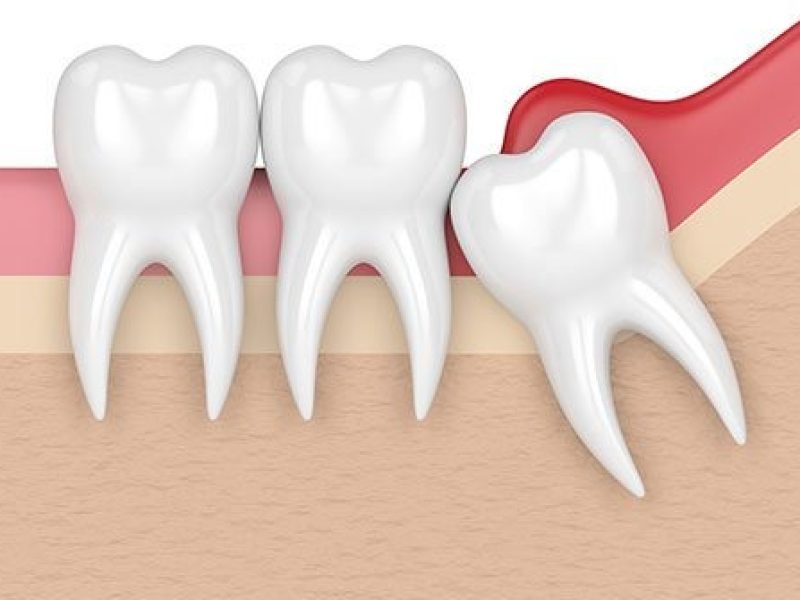

How Impaction Affects Infection Chances

When wisdom teeth come in at an angle that isn’t straight, it can cause overcrowding or damage the gums surrounding them. This impaction makes it harder to clean the teeth in the area, which causes plaque to accumulate. As the accumulated plaque hardens, it becomes tartar which is full of bacteria, which in turn creates inflammation in the area.